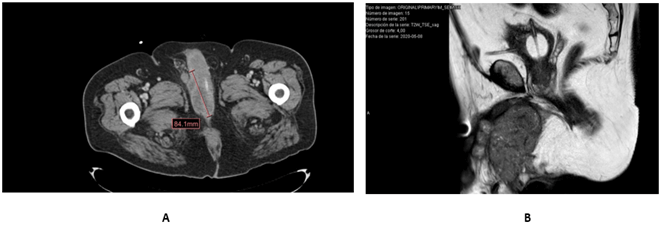

CT scan and MRI reveals a mass with irregular borders with a maximum diameter of 84 mm that invades both corpora cavernosa and the corpus spongiosum, reaching the urethral bulb (Figure 2). The extension study excluded the existence of the lymph node or visceral metastases.

Figure 2: A) Irregular perineal mass affecting both corpora cavernosa; B) Sagittal magnetic resonance image in T2 phase showing a heterogeneous, polylobulated mass that extensively infiltrates both corpora cavernosa and perineal fat.